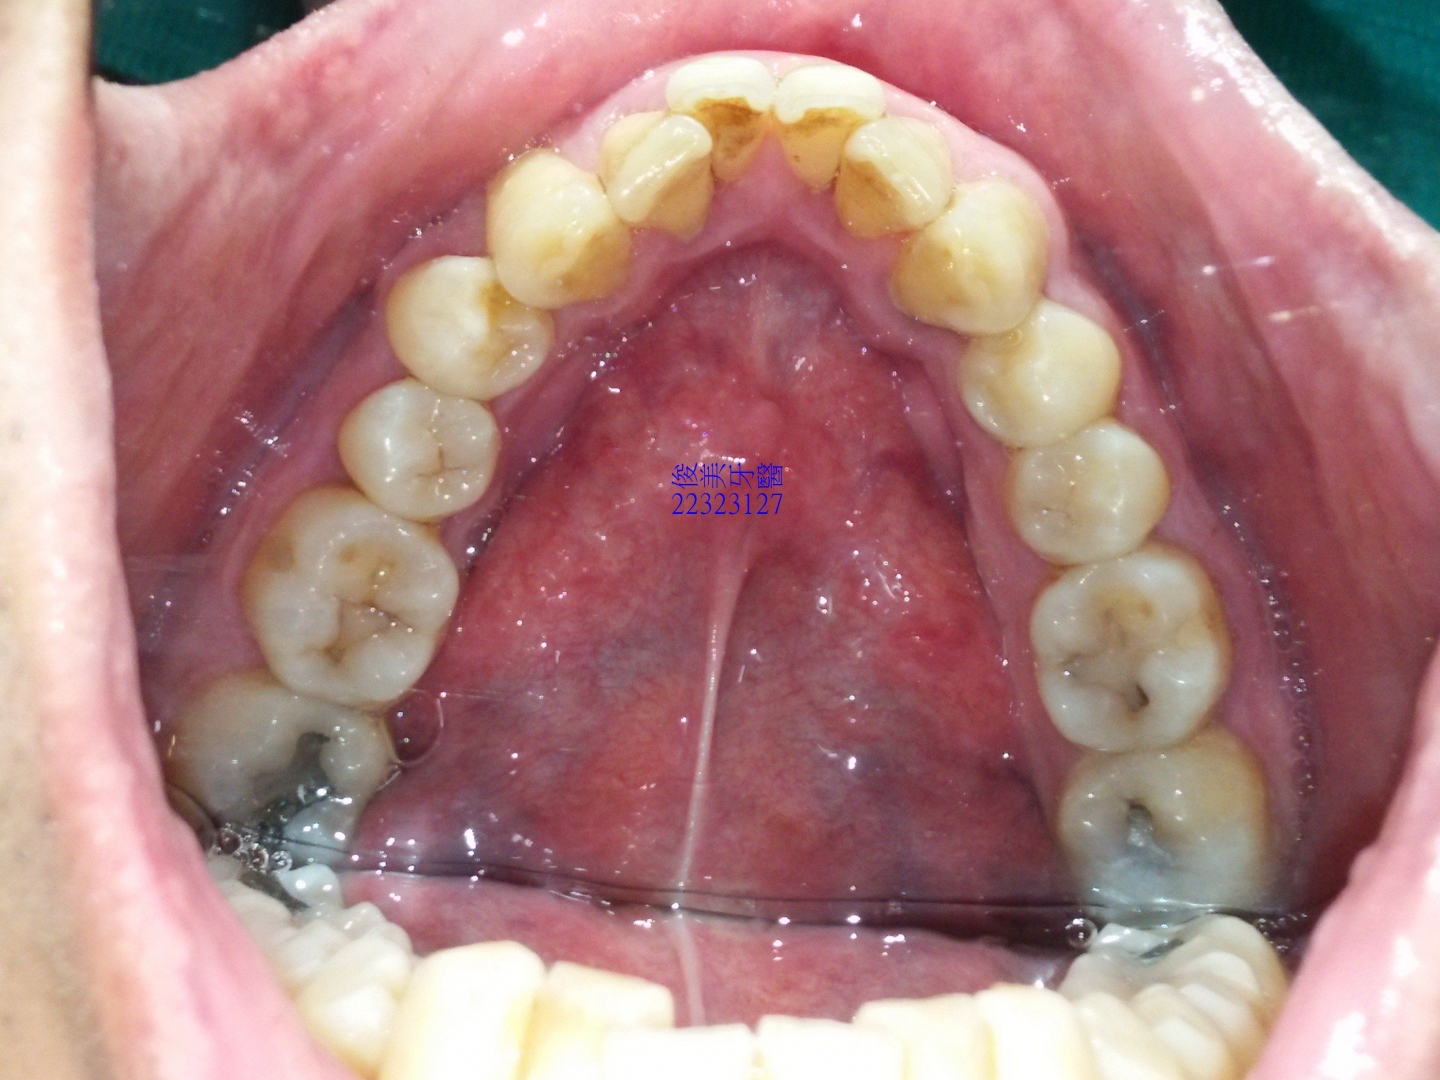

上顎原始狀況。